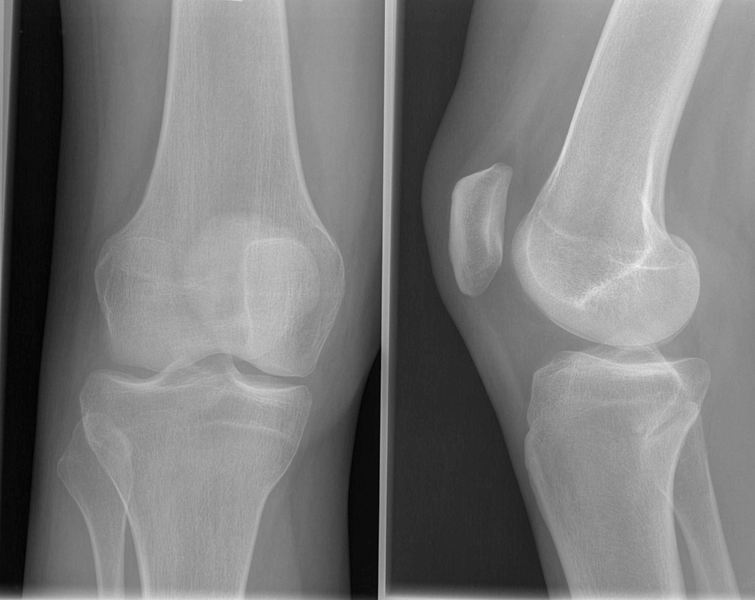

Knie